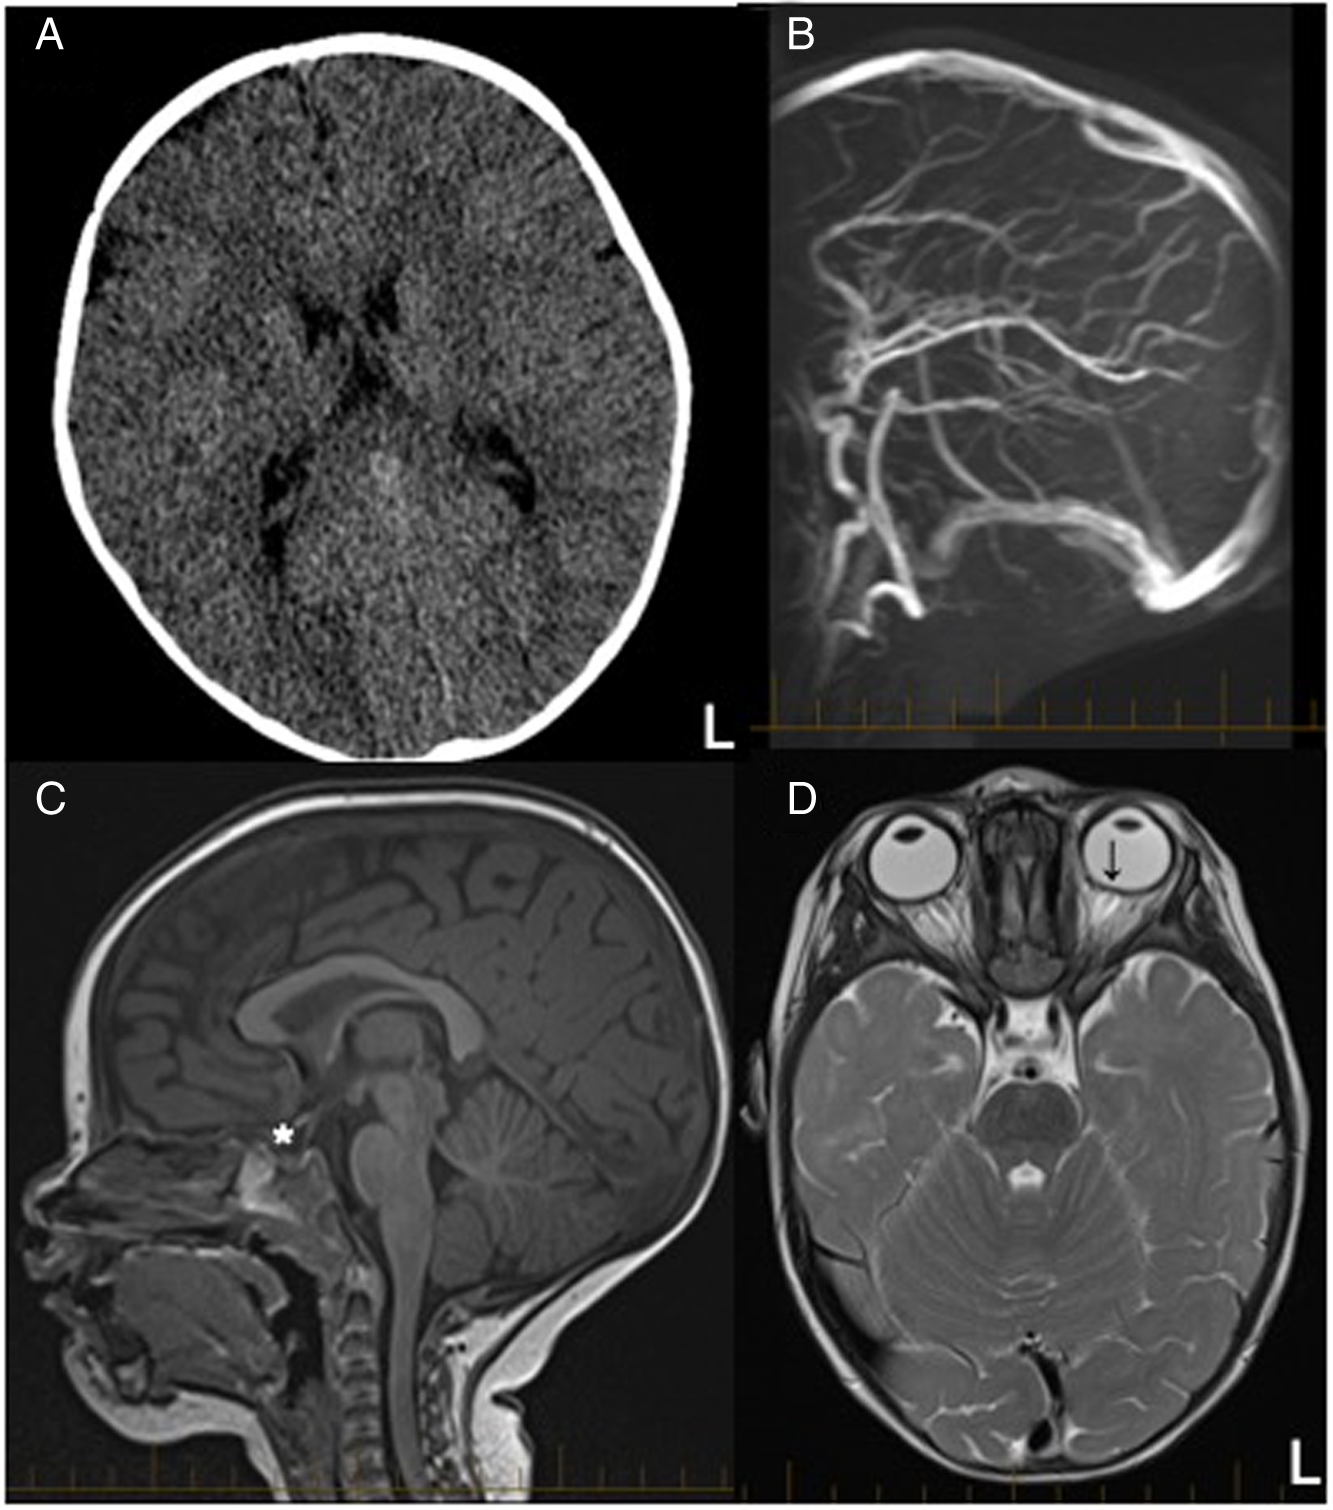

She was irritable with a bulging fontanel, but her neurological and systemic examinations were otherwise unremarkable, though fundi were not visualized. An urgent computed tomography head without contrast was normal (Figure 1A). She underwent a complete septic workup. Under conscious sedation, the lumbar puncture opening pressure was elevated at 34.5 cm H2O (normal range 5–28 cm H2O). Reference Ramkumar, Verma and Crow2 The cerebrospinal fluid (CSF) analysis was reassuring (white blood cells 0, red blood cells 2, protein 0.19 g/L, glucose 3.4 mmol/L). The remainder of her workup revealed only leukopenia (white blood cells 2.9 × 109/L) and increased C-reactive protein (20.8 mg/L). As a precaution, she was started on antibiotics at meningeal dosing.

Figure 1: Neuroimaging evaluation of an infant with intracranial hypertension suspected to be secondary to vitamin A toxicity. Legends: Neuroimaging of acute vitamin A toxicity presenting with intracranial hypertension. (A) Axial CT scan without contrast reported as normal with normal ventricle size. (B) The magnetic resonance venogram confirmed patent intracranial veins and the absence of cerebral sinus venous thrombosis. A developmental variant of a septated descending segment of the superior sagittal sinus was also identified (not shown). T1 sagittal (C) and T2 axial (D) MRI sequences show signs of intracranial hypertension with a partially empty sella (*) and abnormal flattening of the sclera with mild bulging of the head of the optic nerves of the left eye (↓). L = Left.

The next morning, she showed clinical improvement. Her magnetic resonance imaging (MRI) with magnetic resonance venogram revealed no evidence of cerebral sinus venous thrombosis (Figure 1B), but showed signs of intracranial hypertension with mild optic head protrusion in her left eye with a partially empty sella (Figure 1C and D). The ophthalmology assessment did not identify objective signs of visual field deficits, but confirmed “mild” bilateral papilledema without a specified grade.